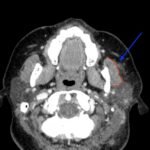

A 36-year-old immunocompetent female presented to the emergency department (ED) with five days of headache and left-sided facial pain. Physical exam showed conjunctival injection of the left eye with multiple vesicular lesions distributed along the V1 dermatome. Labs were remarkable for mild elevation in erythrocyte sedimentation rate (ESR) and c-reactive protein (CRP) with no elevation in white blood cell (WBC) count. Computed tomography (CT) with contrast of the neck revealed soft tissue stranding around the parotid gland. The patient was diagnosed with herpes zoster ophthalmicus (HZO) with concurrent ipsilateral parotitis and subsequently treated with valacyclovir, ofloxacin eye drops, topical erythromycin ointment and amoxicillin/clavulanic acid. Upon follow-up ten days after discharge, the patient noted marked improvement in her symptoms and reduction in pain. To our knowledge, this is the first case described in medical literature of a female patient with HZO and ipsilateral parotitis.